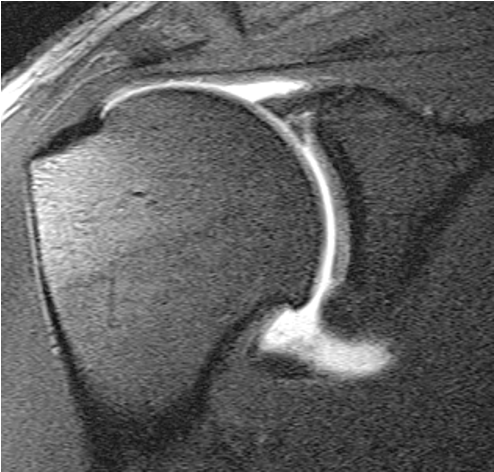

MRI

Spinoglenoid cyst

Spinoglenoid cyst with SLAP tear and posterosuperior labral tear

Differential diagnosis

Posterior labral cysts secondary to glenohumeral OA